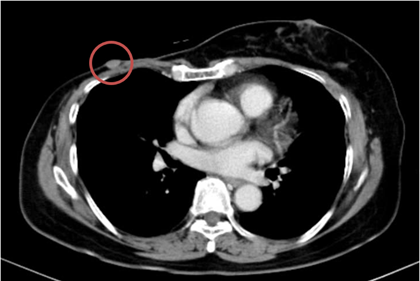

– Chụp cắt lớp vi tính ngực:

+ Thành ngực phải có nốt đặc kích thước khoảng 11x9mm – theo dõi tổn thương tái phát

+ Phổi phải: nhu mô thuỳ giữa và dưới có các khối – nốt đặc, lớn nhất 19x18mm

+ Phổi trái: nhu mô thuỳ trên và đáy phổi sát màng phổi có các khối nốt đặc, lớn nhất 16x17mm

Hình 1. Hình ảnh chụp CT ngực trước điều trị: Tổn thương tái phát thành ngực